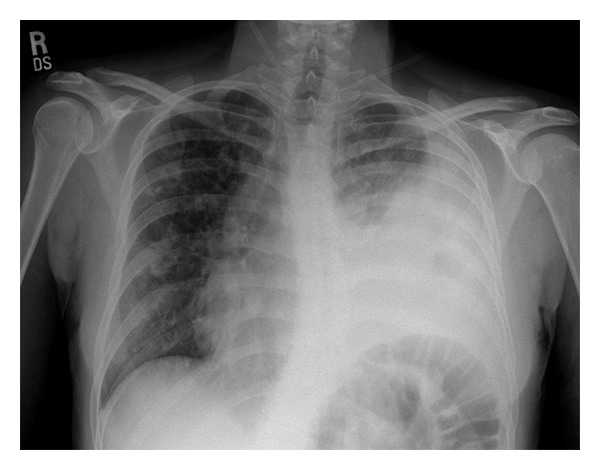

Input 3: What is seen in the X-ray and what should be done?

Visual Med-Alpaca: Bilateral infiltrates and bilateral pleural effusion seen in a chest x-ray may indicate a respiratory infection or other respiratory conditions such as pneumonia pulmonary edema, or pleural effusion, it is important to consult a medical professional for a proper diagnosis and treatment plan.

Automatic Radiology Report Generation (Image-only): near complete opacification of the left hemi thorax with only a small amount of residual aerated lung in the left upper lobe .

Opacification of the lung on an X-ray indicates that there is an abnormality in the lung tissue. In this case, the near-complete opacification of the left hemithorax with only a small amount of residual aerated lung in the left upper lobe suggests that there is likely a significant pathology present in the left lung. Possible causes of this finding include pneumonia, lung abscess, tumor or mass, or pleural effusion (fluid accumulation around the lung). It is important to determine the underlying cause of this finding as soon as possible. A follow-up diagnostic workup may include a CT scan of the chest, sputum culture, bronchoscopy, and/or a biopsy of any suspicious areas in the lung. The appropriate treatment will depend on the underlying cause, but it may include antibiotics, drainage of any fluid collections, or surgery to remove any masses or tumors. Prompt evaluation and treatment are necessary to prevent complications and improve outcomes.